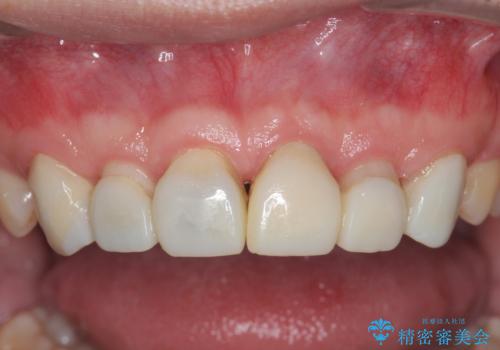

歯周外科を行い、歯ぐきの状態を整えた前歯セラミック治療

- 「前歯の見た目、歯ぐきの腫れを改善したい。」と希望され来院されました。

前歯には接着性の維持装置や、中途半端な形の連結クラウンが装着され、清掃性が悪く歯ぐきの腫れや、歯ぐきの形態の不揃いが認められました。

歯周外科を行ったことで、歯ぐきの形態や腫れが改善され、審美性だけでなく清掃性も大きく改善することができました。